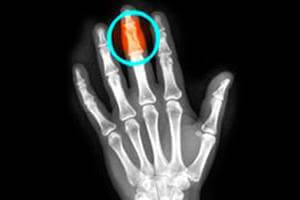

Приблизительно 50% травм ногтевого ложа, требующих вмешательства хирургов, связаны с переломами дистальных фаланг. При травме пальца обязательно нужно пройти рентгенографию. Код повреждений по МКБ-10: S60.

перелом дистальной фаланги может быть закрытым, т.е. не видимым глазу. Может возникнуть при падении, ударе по фаланге тяжелым предметом. Даже если отсутствует деформация пальца, нужно сделать рентгеновский снимок.